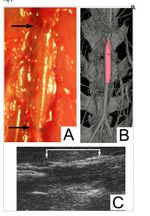

Various tissue engineering methods for creating blood vessels include 3D printing, decellularized native vessels, synthetic biopolymers, and cell sheets that create tubular structure with various degrees of success [27]. Previously engineered autologous engineered arteries had poor mechanical properties. Furthermore, the aged smooth muscle cells of previous models have less proliferative capacity and collagen production. The process of decellularization of native vessels, however, maintains mechanical properties and produces less immunologic responses. In one study, the process of decellularization was used to create an allogeneic matrix. Human smooth muscle cells were seeded onto a scaffold poly-glycolic acid (PGA) mesh over a 1-mm diameter silicone tube using a perfusion system. The human tissue-engineered vessels were decellularized and implanted into nude rats, shown by various imaging techniques in Figure 10, for the evaluation of the vessel as an arterial graft [27]. The human TEV presented similar mechanical properties to that of a typical human blood vessel. Burst pressure, or the point at maximum pressure before the blood vessel breaks, was similar to humans (1,567 ± 384 mm Hg (n = 3) versus 1,680 ± 307 mm Hg for human vein [27]. Histological anaylsis also demonstrated the growth of of endothelial and smooth muscle cells [27]. Transmission electron microscopy further demonstrated the growth of elastin in the neointima and collagen fibers [27]. Limitations of this study, however, are the small sample size and short-term studies. Long-term results are needed to investigate any late side effects, such as stenosis, or the abnormal narrowing of the blood vessel.